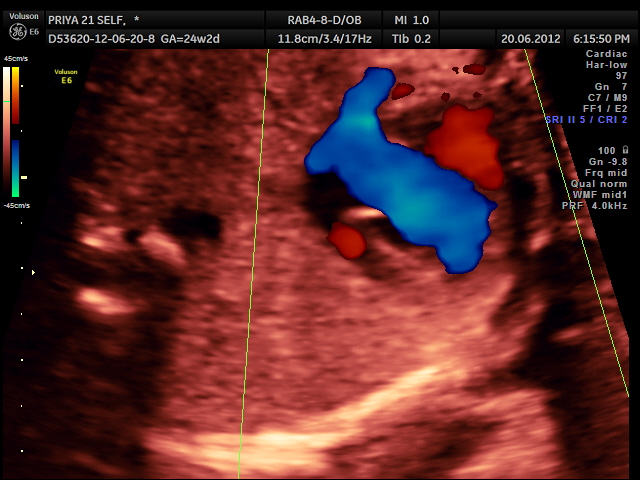

the following video shows right atrium and rt ventricle to be grossly dilated and the left atrium and left ventricle to be very small and hypoplastic.